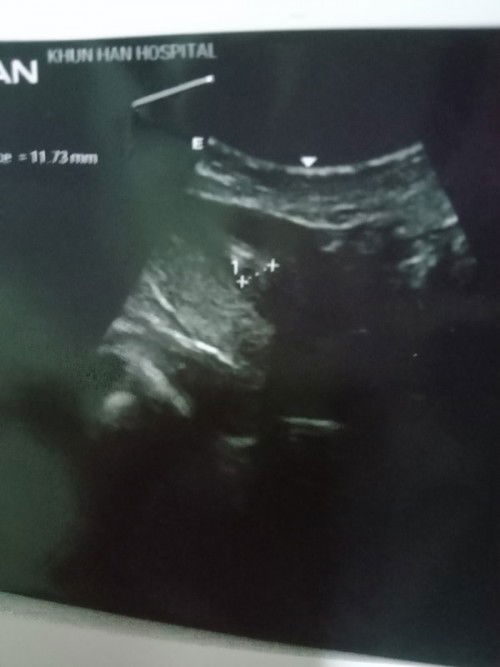

เมื่อวาน15/9ไปซาวด์ดูน้องมาไม่เห็นถุงอะไรเลยค่ะแม่ๆ ปจด มาครั้งล่าสุด4 /8 พยาบาลนับได้ว่า 6วีค

หมอเลยเจาะเลือดดูฮอร์โมน นัดฟังผล22/9แม่แอบกังวลกลัวท้องน้องมดลูกจังค่ะ🥺🥺 #ขอบคุณล่วงหน้านะคะ #ขอคำแนะนำหน่อยค่ะ